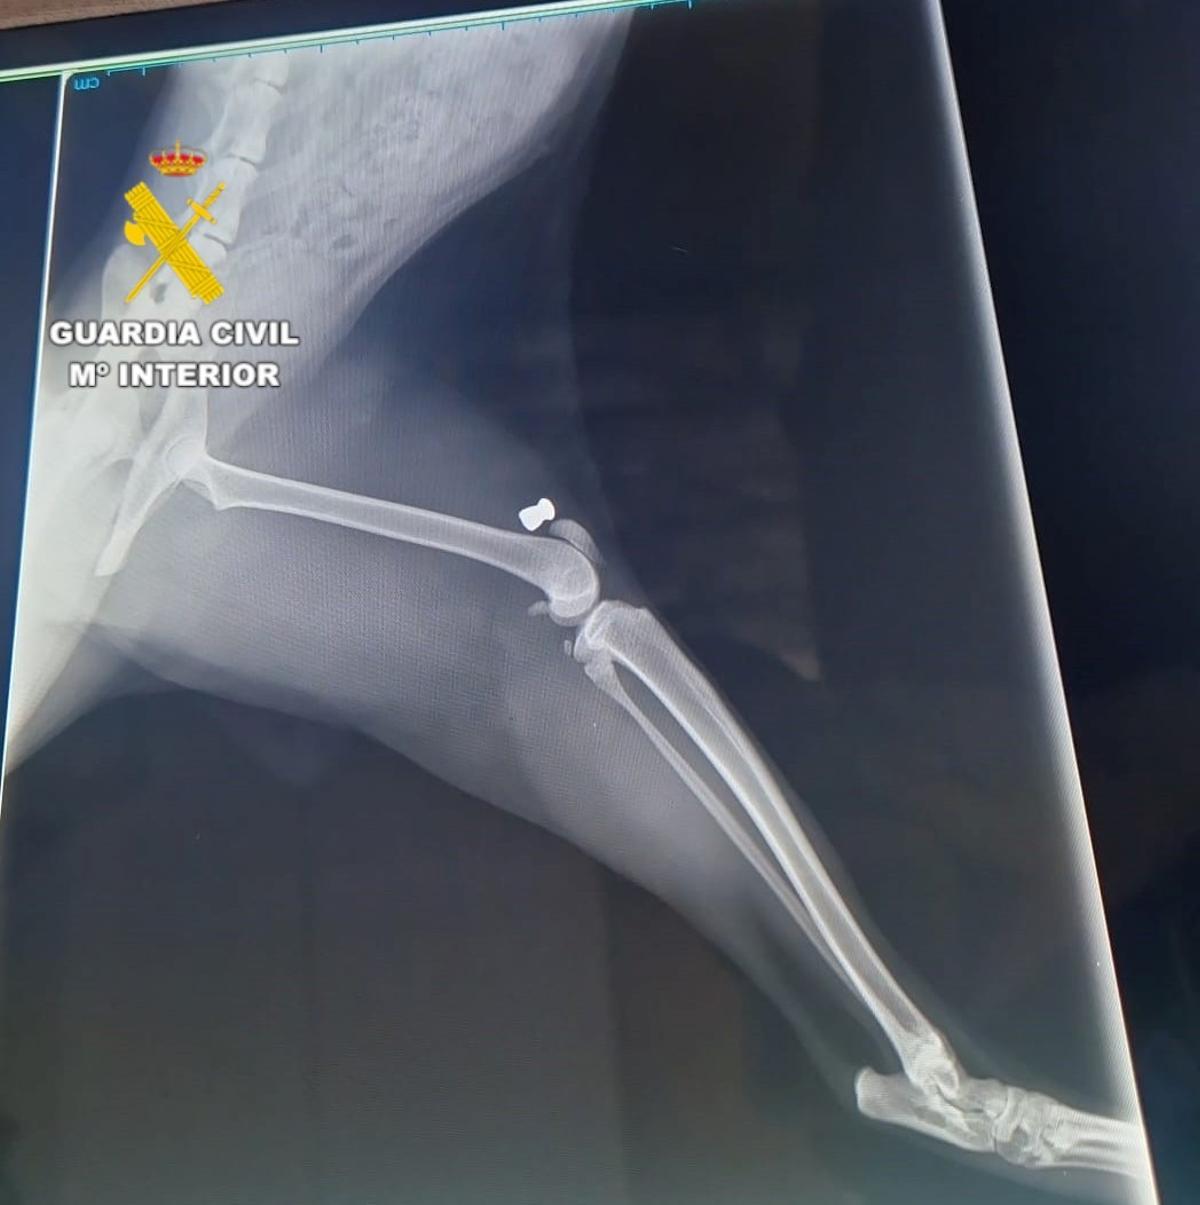

Radiografía que muestra la presencia de un perdigón en el cuerpo de un gato. / Guardia Civil

Durante el mes de septiembre se inició una investigación tras la muerte de tres gatos en el municipio. Además, otros doce presentaban heridas. Durante las pesquisas, los agentes comprobaron que las lesiones eran compatibles con las producidas por impacto de perdigón de carabina de aire comprimido.

Tras un examen realizado por un veterinario, se confirmó ese extremos y hallaron varios perdigones incrustados en el cuerpo de los animales.